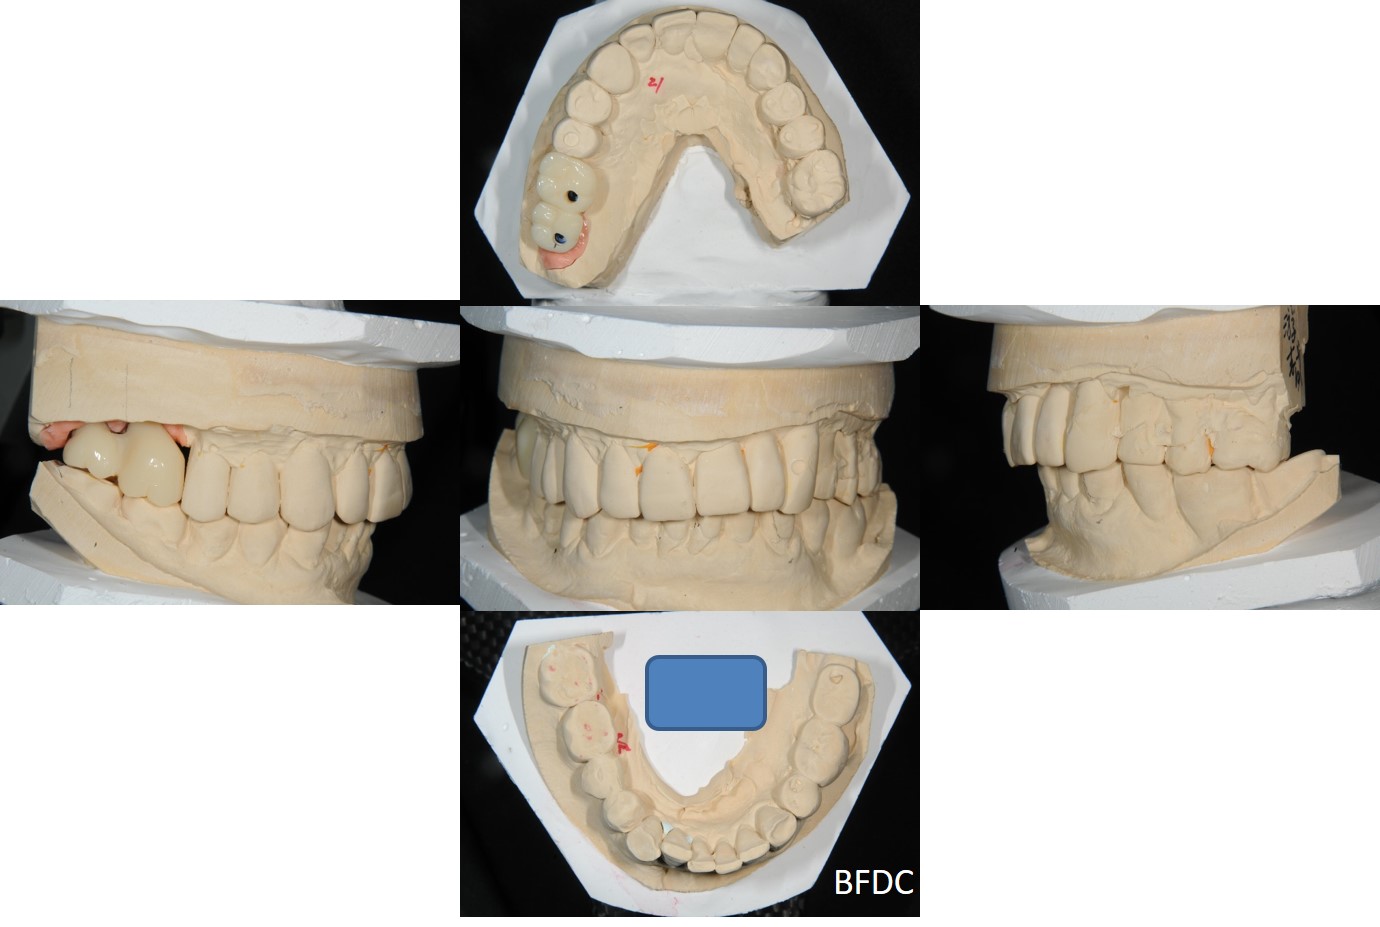

骨癒合後,植體印模,上咬合器